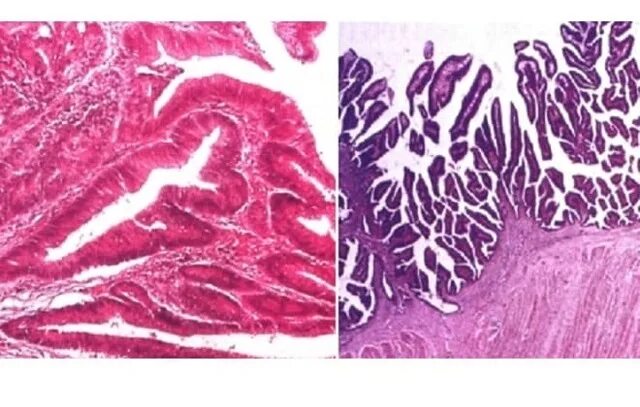

Полип микровезикулярного типа толстой кишки